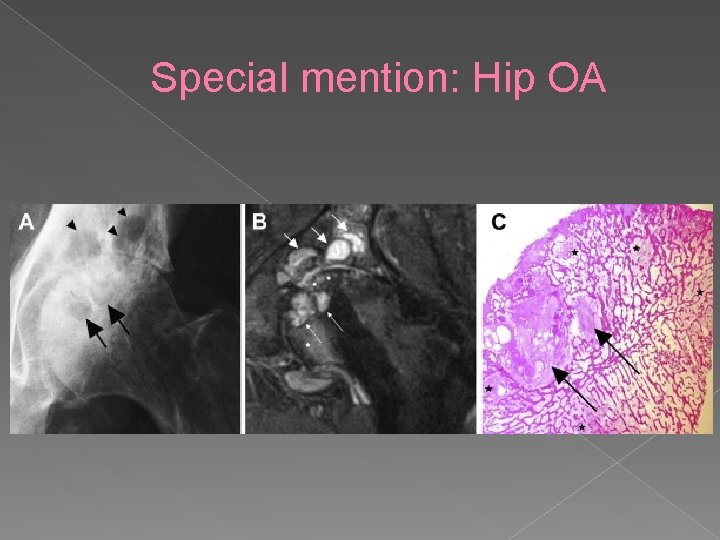

Special mention: Hip OA Hip – spherical structure • Thin covering of articular cartilage • More difficult assessment than the knee • Other features seen: • › › Labral changes/hypertrophy Paralabral cysts Loose bodies Dysplasia

Special mention: Hip OA

Special mention: Hip OA